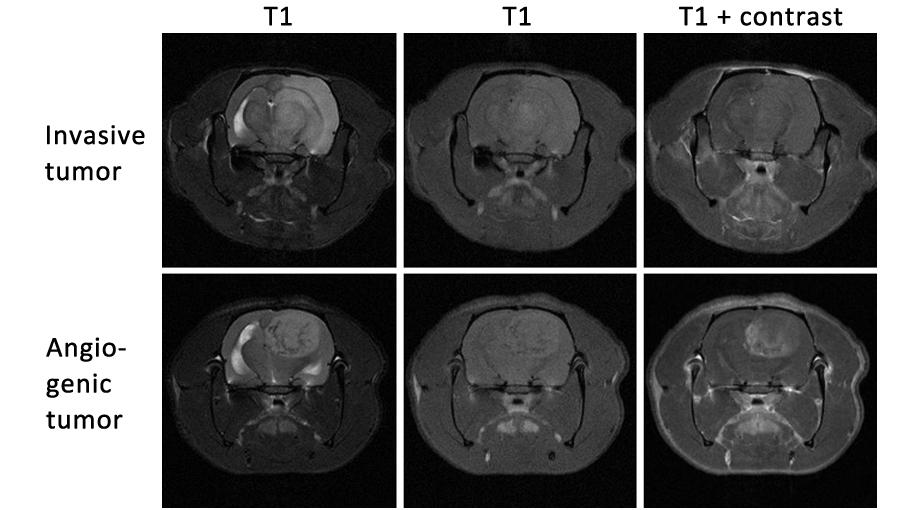

To achieve these goals, we use a human GBM xenograft model that recapitulates the invasive and angiogenic features of patient tumors. This model has been developed within the Translational Cancer Research lab and is one of the most clinically relevant animal models available. Using this model, we have shown that lentiviral vectors delivering a suicide gene can efficiently kill GBM cells and significantly prolong survival. In another project, we have shown that activation of the wild-type EGFR promotes invasive and angiogenesis-independent growth of GBM.

Within our projects we use MRI and confocal imaging. From the MIC equipment, we have used the 7 tesla MRI and the Zeiss confocal microscope.